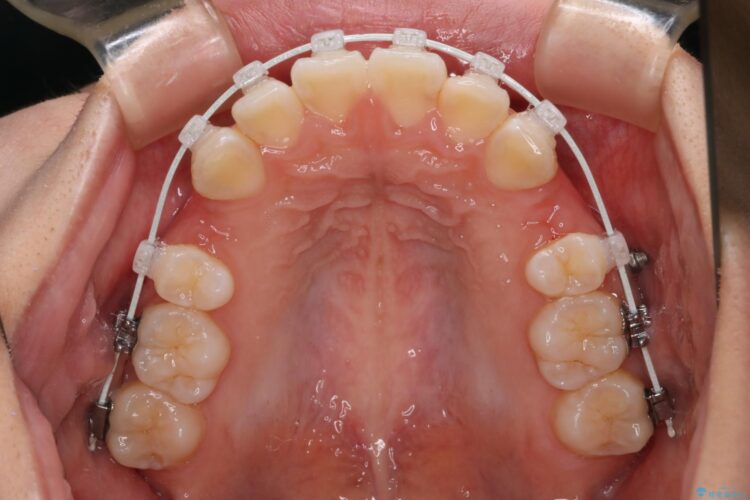

上下4番目の歯を抜歯してガタつきを改善しながら口元を下げる治療計画を立てました。

抜歯矯正で口元を下げたことで、Eラインが大変綺麗になりました。